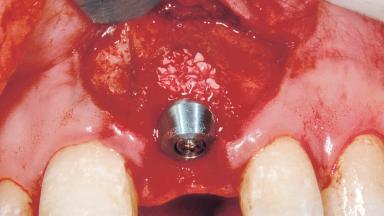

Immediate Placement of an Implant in a Maxillary Left Central Incisor Site

| Bone Augmentation | Horizontal|Simultaneous |

| Augmentation Materials | Xenogenous|Membrane |

| Soft Tissue Grafting | Simultaneous |

| Placement Protocol | Immediate implant placement |

| Bone Volume | Damage to one or more socket walls |